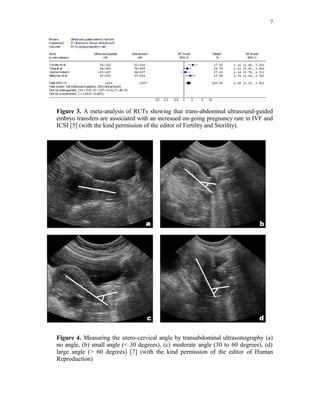

Figure 3. A meta-analysis of RCTs showing that trans-abdominal ultrasound-guided

embryo transfers are associated with an increased on-going pregnancy rate in IVF and

ICSI [5] (with the kind permission of the editor of Fertility and Sterility).

Figure 4. Measuring the utero-cervical angle by transabdominal ultrasonography (a)

no angle, (b) small angle (< 30 degrees), (c) moderate angle (30 to 60 degrees), (d)

large angle (> 60 degrees) [7] (with the kind permission of the editor of Human

Reproduction)

Performing ET with a full bladder to straighten the utero-cervical angle has been

claimed to improve pregnancy and implantation rates [6]. We have also found that the

utero-cervical angle measured by ultrasound is related to the pregnancy and

implantation rates (figure 4) and that patients with acute utero-cervical angles (>60

degrees) had significantly lower pregnancy rates compared to patients with no angles

[OR= 0.36, 95% CI (0.16 – 0.52) [7]. Moulding the catheter according to the

measured angle resulted in a lower incidence of difficult transfers [(OR= 0.25, 95% CI

(0.16 - 0.40)] as well as higher pregnancy rates [(OR= 1.57, 95% CI (1.08 – 2.27)].